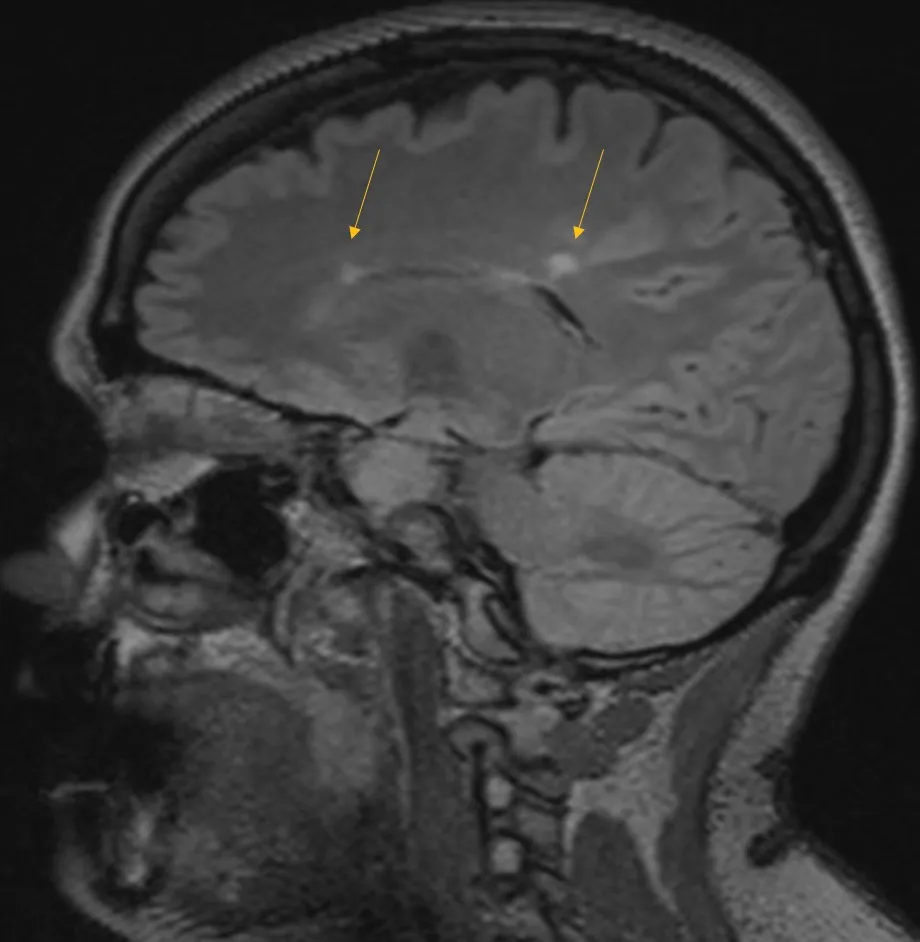

2021 Brain MRI

She had an actively enhancing juxtacortical lesion present in the left temporal region.

In 2021, she began to develop numbness in her right arm and hands that progressed over one month to encompass her left arm and hands. She was seen at AdventHealth Neurology in Winter Park and underwent further testing that included MRI of the brain, cervical and thoracic spine. As her previous images were compared to her current images, she was found to have previous lesions in the brain located in the periventricular and infratentorial region of the brain, which are common locations for lesions of MS.